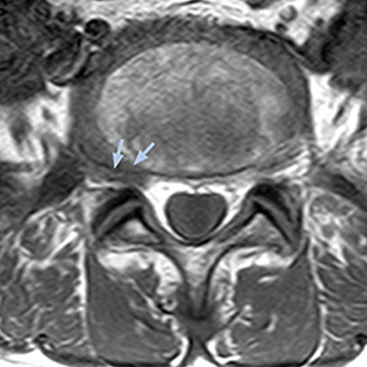

The key concept in MR neurography, Dr. Yabuki stresses, is the ability to directly visualize spinal nerves, versus inferring the presence of pathology indirectly. “Before NerveVIEW, we estimated compression of the nerve by looking for the presence or absence of fat signal on other MR images,” he says.

“For example, in sagittal images, when the presence of fat is observed in the intervertebral foramen, it suggests that there is a margin around the nerve. Similarly, the absence of fat indicates that the nerve is being compressed. So, we used to deduce nerve compression indirectly. With NerveVIEW, however, we can observe the condition of the nerves directly, regardless of the presence or absence of fat. We always prefer such direct observation of anatomy over having to make an inference about it.”

According to Tanji, methods such as ProSet FFE, STIR or 3D VISTA are anatomically nonselective because background signals, for instance from blood vessels, often interfere with nerves, which hampers evaluation of details, especially at the peripheral side of the nerves.

“The intra-luminal signal of veins, especially around the intervertebral space, can be suppressed well with NerveVIEW. As a result, we can easily observe the detailed nerve structure around the posterior ganglion,” he says. “This is why we use 3D NerveVIEW for intraforaminal stenosis and extraforaminal stenosis/herniation (lateral disc herniation). On the other hand, if herniation is suspected to exist inside the dorsal root ganglion (DRG), balanced TFE or ProSet-FFE is applied. NerveVIEW is not suitable for evaluating the median type of herniation.”